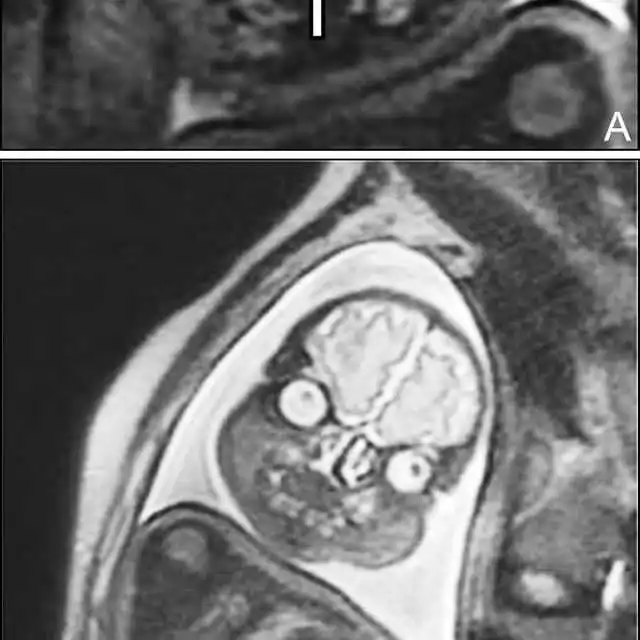

"Поздравляем, у вас демон": жуткий МРТ-снимок беременной женщины

Всегда подмечал в голливудских фильмах такое клише: беременной девушке делают УЗИ, а потом показывают матери и отцу эмбриончик, после чего все начинают умиляться, охать и обниматься, несмотря на то, что на экране по сути ничего не видно. В которой раз можно убедиться в том, что в мелодрамах правды нет. Это подтверждают жуткие МРТ-снимки беременной женщины из реальной жизни. Честно скажу, мне это сегодня приснится. Впечатлительным я бы рекомендовал не смотреть.